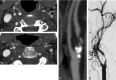

Fig 1.

Measurement of the internal carotid artery stenosis in CTA axial images according to NASCET. A, Maximal stenosis in left ICA. B, Normalized vessel diameter. The reference point was chosen so that diameters are the same over a distance.